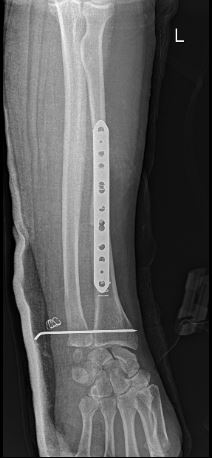

Xrays

Before surgery After Surgery